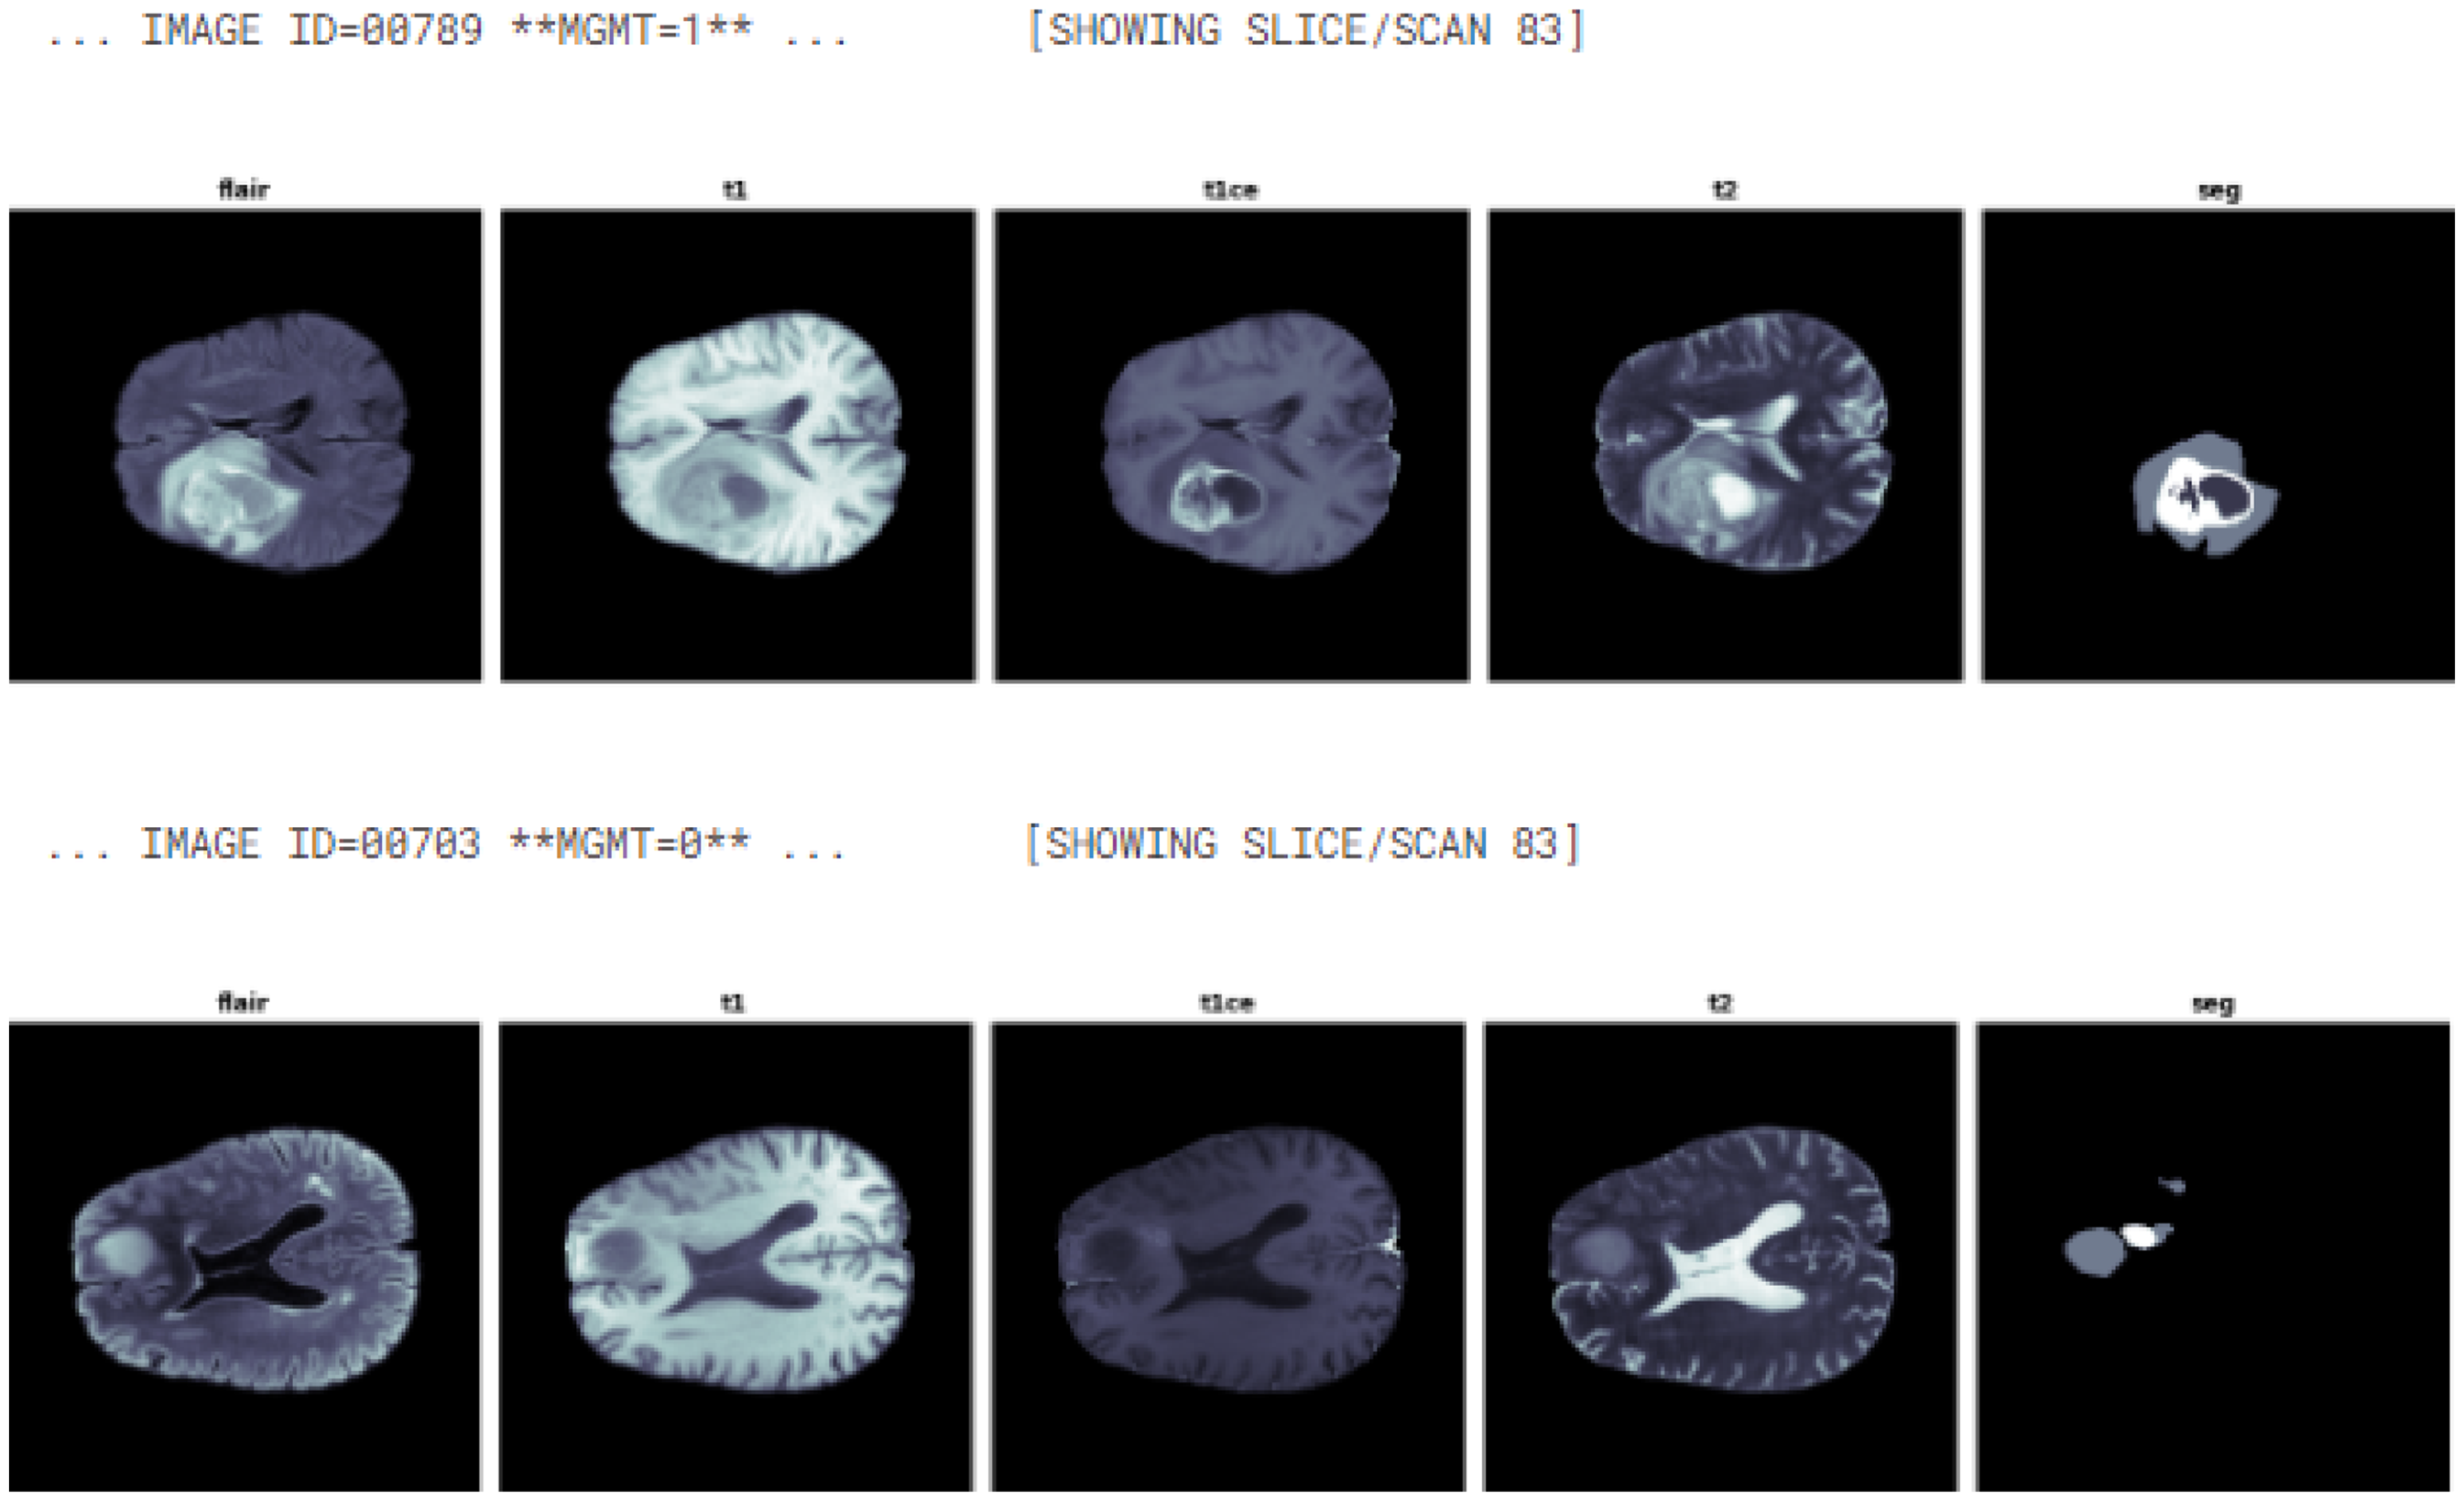

Each modality has a dimension of 240 by 240 pixels with 155 different slices. Figure 1 illustrates a sample from the benchmark BraTS2021 dataset, showcasing all four modalities along with the MGMT label of slice number 83.

Multimodal MRI scan was taken at axial view of patient IDs 789 and 703 with segmentation and MGMT label.